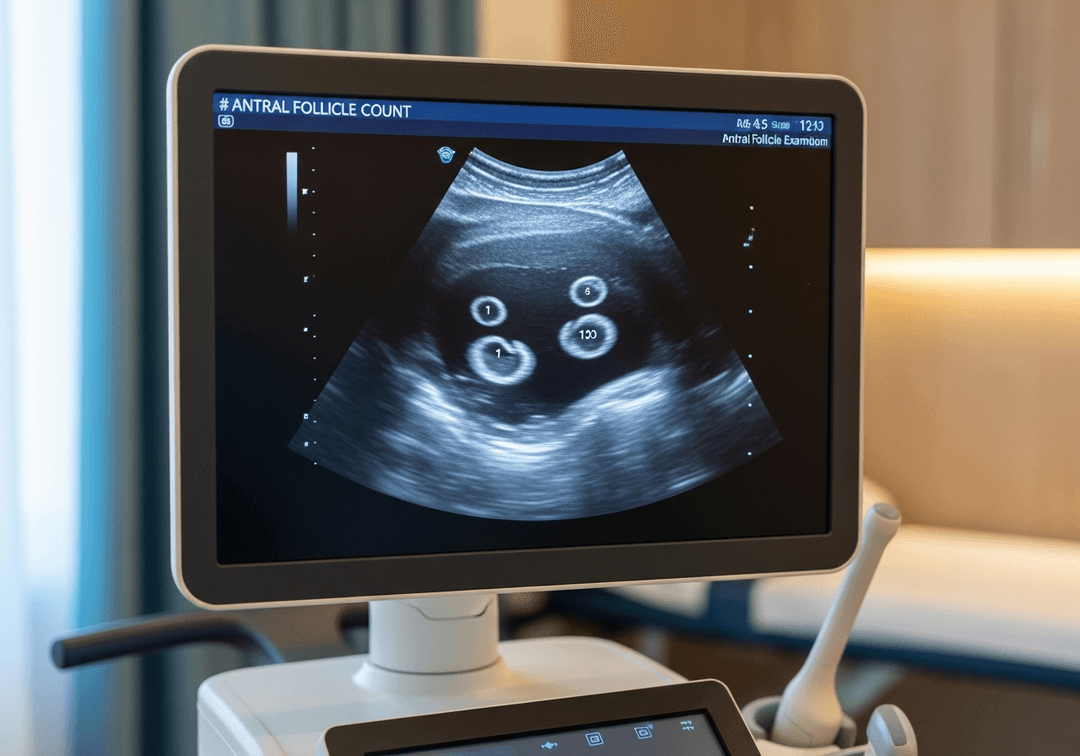

Le comptage est réalisé par échographie endovaginale, idéalement entre J2 et J5 du cycle. L'échographiste visualise chaque ovaire et compte tous les follicules mesurant entre 2 et 10 mm de diamètre.

- Examen rapide (10-15 minutes)

- Échographie endovaginale pour une bonne visualisation

- Comptage sur chaque ovaire

- Mesure du volume ovarien

Le CFA doit être réalisé en tout début de cycle (J2-J5) pour une mesure fiable, avant que les follicules ne commencent à grossir.